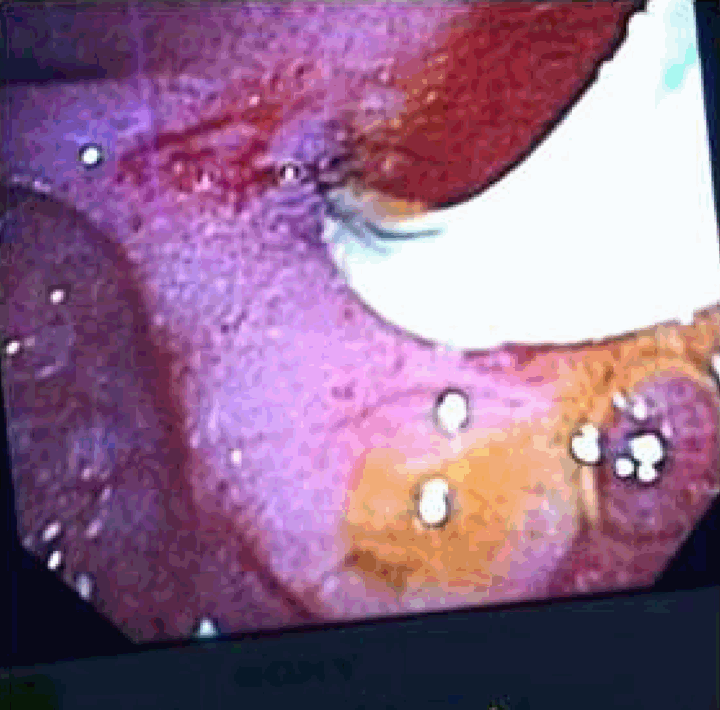

A 43-year-old female presented with severe right upper quadrant abdominal pain, nausea, vomiting and diarrhea for four days. Three years ago, she was admitted for cholecystitis, cholelithiasis and cholangitis requiring an endoscopic retrograde cholangiopancreatography (ERCP) with plastic stent placement for drainage. Unfortunately, the patient was lost to follow-up after initial plastic stent placement. On admission, she was afebrile and her liver function tests were normal. The ERCP was performed which revealed the distal end of the biliary stent, perforating proximal to the periampullary area causing a large choledochoduodenal fistula (Figure 1). The guidewire was successfully negotiated through the native papilla as well as the fistulous tract. No obstruction, mass or stone was noted. A sphincterotomy was done through the fistula (Figure 2) and through the actual sphincter at the ampulla (Figure 3). The sump was opened, swept clean with removal of abundant debris. Her abdominal pain completely resolved and patient clinically improved within 24 hours after the procedure. | ||||||